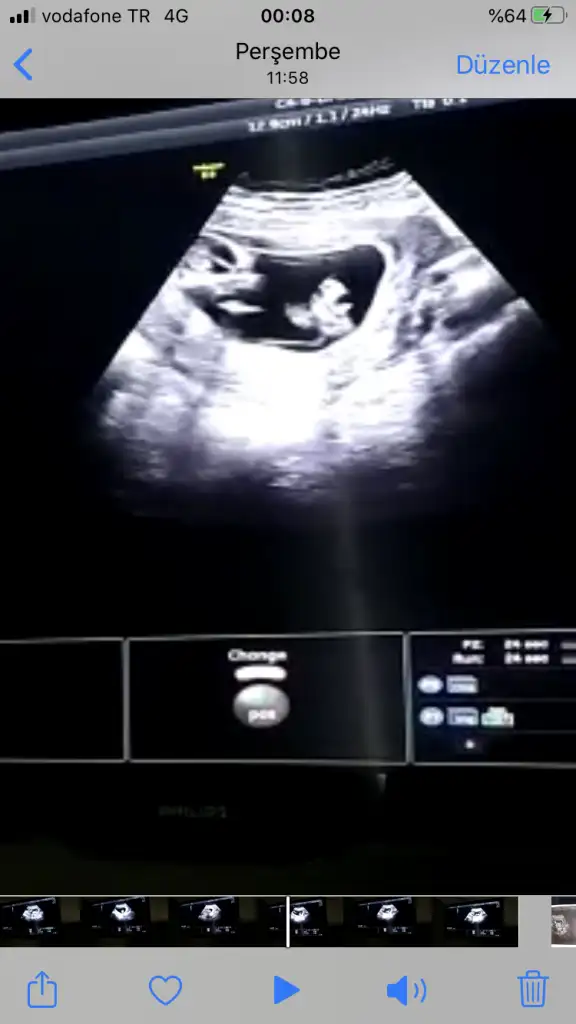

Erkek gibi ama nubun birazını dr + getirmiş emin olamadım başka usg varsa paylaşın

12+2 bana da yorum yaparmısınız, doğru gönderebildim mi bilemiyorumDr + tam nuba denk getirmiş başka usg varmı![]()

12+2 günlük, bana da yorum yapabilir misiniz

Kız gibi